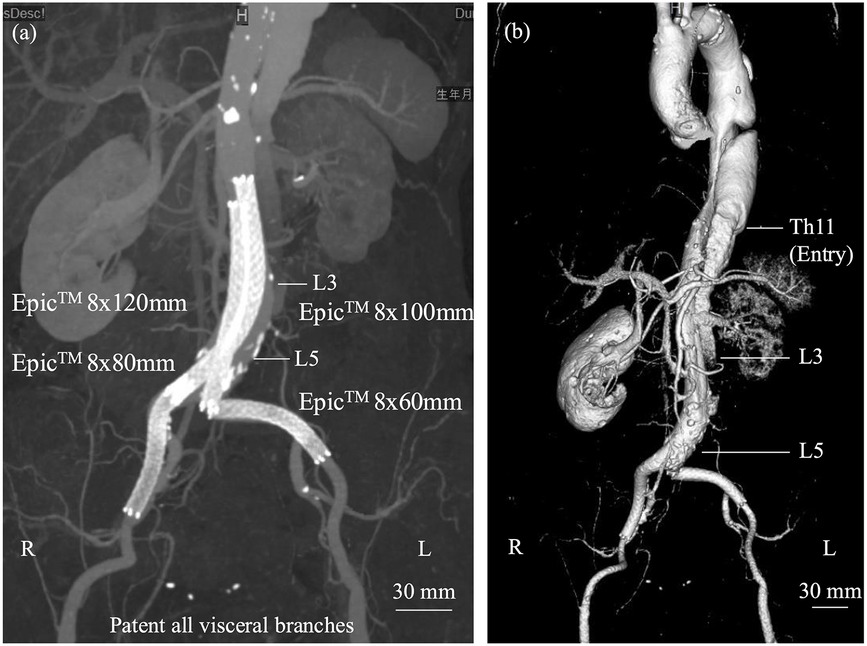

We report a rare, life-saving endovascular intervention in a patient with acute type B aortic dissection (TBAD) complicated by severe lower limb ischemia due to dynamic obstruction. A 67-year-old woman, previously diagnosed with uncomplicated Stanford type B dissection with a thrombosed false lumen, suddenly developed bilateral leg pain and absent distal pulses on day 12. CT revealed a new entry tear in the descending aorta, leading to false lumen reperfusion and collapse of the true lumen at the abdominal aorta and both common iliac arteries. As appropriate thoracic endovascular aortic repair and endovascular aortic repair devices were not immediately available, emergency repair was performed using four self-expanding bare-metal stents via bilateral femoral access. This achieved prompt true lumen re-expansion and restoration of distal pulses. Post-procedure imaging confirmed improved perfusion. Although extra-anatomical bypass is often considered, complete collapse of the abdominal true lumen made it unlikely to be effective. This case demonstrates that widely available bare-metal stents offer a practical and effective emergency option for restoring distal perfusion when standard devices are not accessible. Importantly, this approach should be regarded as palliative for limb salvage rather than definitive treatment of the entry tear.